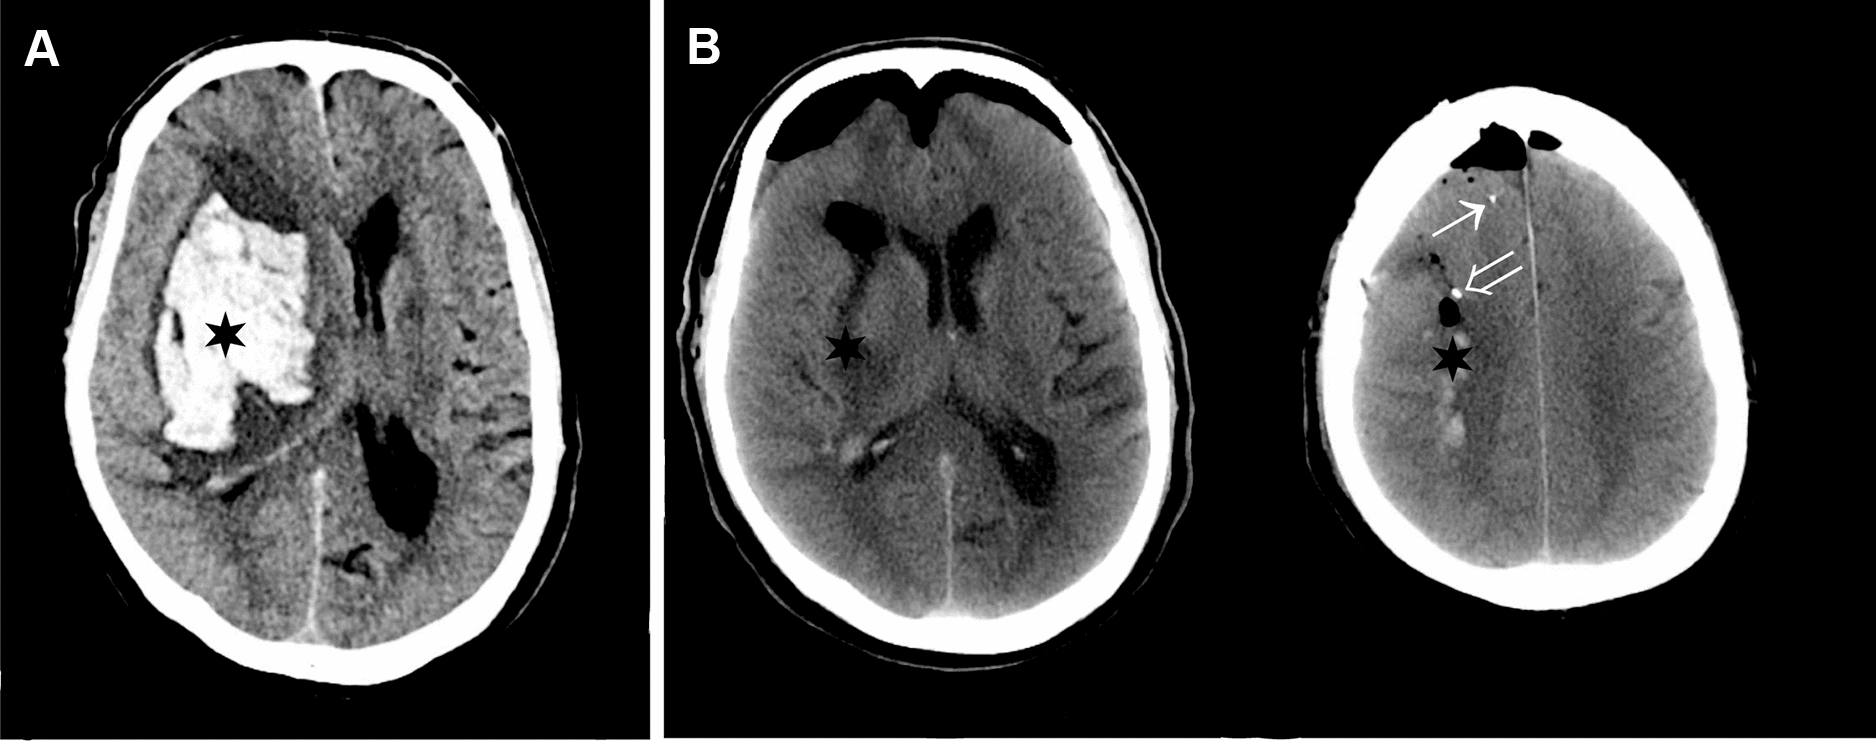

Ten patients (eight men, two women; Table 1) underwent surgery with evacuation of ICH and placement of dual MD catheters (Fig. 1a, b). None of these patients had intraventricular hemorrhage, and an external ventricular drain (EVD) was not inserted. ICP monitoring was initiated in three patients using a parenchymal ICP monitor. Median age was 64 (51–71) years; median time to surgery from ICH onset was 27.8 (6–82) hours and median MD-sampling time was 95 (50–148) h. Mean distance from MD catheter to evacuated ICH was 6 (± 5.0) mm for the PHZ catheter and 24.5 (± 7.6) mm for the SNX catheter. Mean volume of ICH was 77 (± 25.8) ml (Table 1). The PHZ catheter of patient 10 was not placed according to protocol (> 10 mm from ICH), however, on CT control, it was located in tissue affected by the ICH and was included in the analysis. The SNX catheter of patient 7 was placed in tissue which subsequently developed an ischemic infarction thus not representing normal cortex, and the data from this MD catheter was excluded from further analysis. White blood cell count was 9.6 (± 1.9), 10.1 (± 1.6), and 9.2 (± 2.5) × 109 at 6–10 h, 20–26 h, and 40–46 h, respectively. C-reactive protein was 25.7 (± 28), 99.3 (± 72) and 131.4 (± 78) mg/l at 6–10 h, 20–26 h and 40–46 h, respectively. Functional outcome at 12-month follow-up is presented in Table 1.

Fig. 1

Preoperative and postoperative CT scan. a, Preoperative CT scan of a 68-year-old man presenting with an intracerebral hemorrhage (ICH) (black star) in the right basal ganglia. b, Following surgical evacuation of the ICH, a postoperative CT scan shows the hematoma cavity (black star) and the tip of the microdialysis (MD) catheters placed in the perihemorragic zone (PHZ) open arrow and seemingly normal cortex (SNX) (closed arrow), respectively. CT= computed tomography